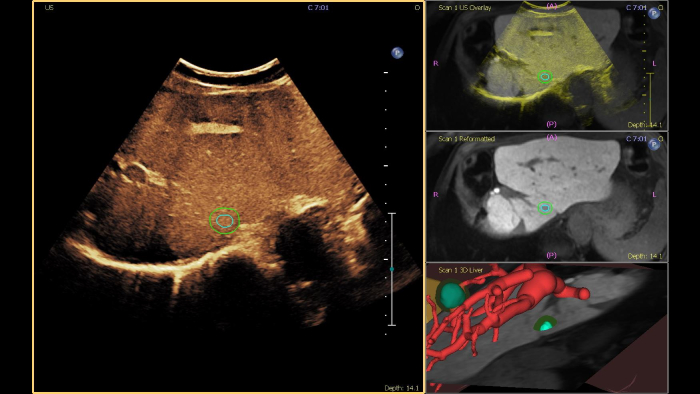

Os ecógrafos da Philips para a radiologia de intervenção suportam uma gama de capacidades sofisticadas para aplicações de intervenção. O fluxo de trabalho otimizado permite aos médicos alcançar uma fusão rápida e eficaz de TAC/RM/PET/CBCT com ecografia em tempo real, enquanto a navegação da agulha ajuda a orientar a biópsia e a ablação das lesões pequenas e de difícil acesso. A fusão e a navegação também podem ser utilizadas em conjunto com a ecografia com realce por contraste (CEUS), dando aos médicos acesso a ferramentas de diagnóstico ainda mais poderosas com visualização avançada.

Obtenha um alinhamento bem-sucedido dos volumes de TAC ou RM com a ecografia em <1 minuto para a caracterização eficaz das lesões. O registo de duas modalidades de imagiologia através de métodos convencionais pode ser demorado e tecnicamente difícil, demorando frequentemente até 10 minutos para alcançar uma fusão bem-sucedida.

Esta ferramenta semiautomatizada ajuda a delinear um contorno 3D à volta de uma estrutura de interesse, melhorando a orientação do procedimento mesmo em casos tecnicamente difíceis em que a lesão pode não ser visualmente óbvia ao nível de ultrassom. A lesão pode ser apresentada em 3D ou 2D através de uma modalidade complementar e sobreposta na ecografia ou TAC em tempo real, ajudando a visualizar a localização em relação às estruturas críticas circundantes.

Oferecer o único fluxo de trabalho de intervenção da indústria com navegação da agulha apenas para TAC num ecógrafo, a fusão de imagem e a navegação da agulha desbloqueiam a flexibilidade e abrem novas possibilidades ao tornar a fusão de imagem e a utilização de imagiologia por ecografia totalmente opcional. A localização da agulha em relação à TAC é acompanhada e atualizada em tempo real para visualização do procedimento, permitindo que os profissionais de saúde abordem casos e anatomias complexas, mesmo quando a imagiologia por ecografia não é possível. Tecnologia de acompanhamento contínuo do paciente. Assim que o passo de registo estiver concluído, o paciente pode mover-se, mudar de posição e o gerador de campo pode ser movido para dentro ou para fora do espaço do procedimento sem perder pontos de referência anatómicos ou diminuir a precisão do acompanhamento.